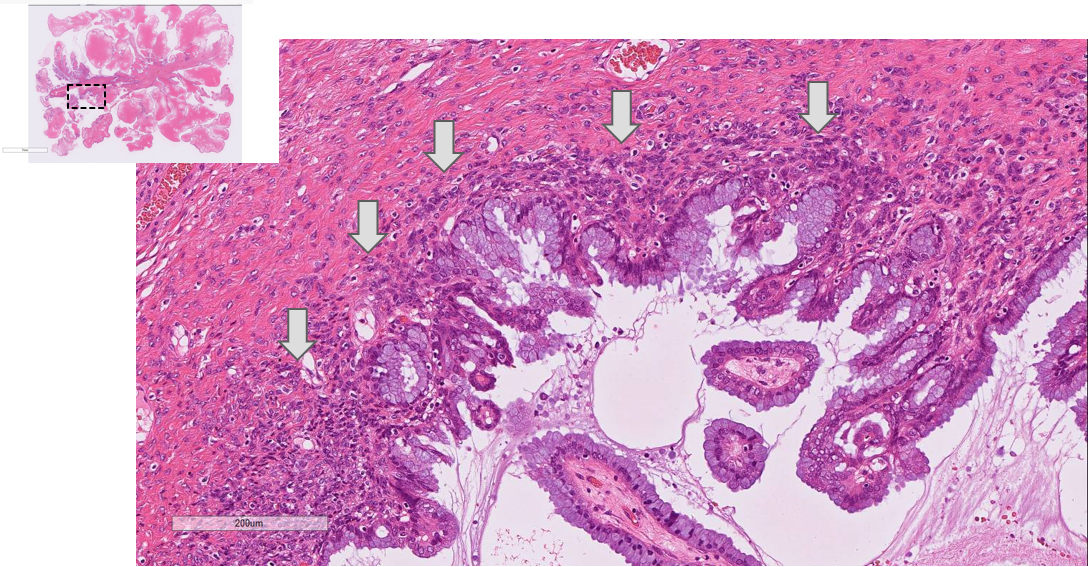

• HE(x20) Stalk 部分拡張血管や dense な線維性結合組織成分を認める

• HE(x40) 辺縁部分 ①浮腫状間質を取り囲み、腫瘍細胞が低乳頭状に増殖する。 矢印:腹腔内に粘液が漏出

• HE(x100) 辺縁部分 ② 細胞質内粘液を有する内頸部型の粘液円柱上皮が低乳頭状に増殖。

矢印:上皮下には内膜間質様の細胞密度の高い間質を認め、間質浸潤はない。